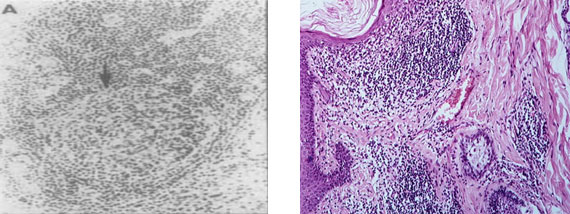

На рис. 6 представлены фото фолликулоподобных структур в синовиальной оболочке при РА. Видно, что эктопические герминативные центры находятся на разных стадиях своего формирования и функционального состояния. Наличие очагов эктопического лимфоидного неогенеза с герминативными центрами позволяют выделить определённые патофизиологические варианты РА [31].

Рис. 6. Видны множественные эктопические герминативные центры (фолликулоподобные структуры) в синовиальной оболочке при РА на разных стадиях своего развития (Х 100), по материалам [78]